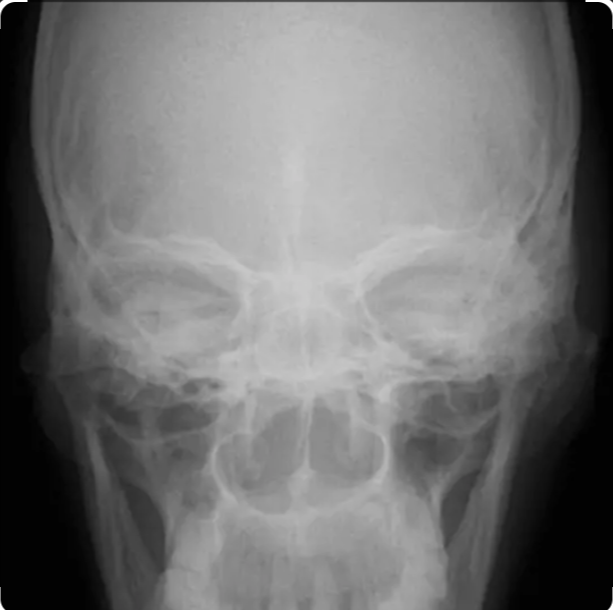

X-Ray Maxilla AP View

Medifyhome is now available for X-Ray Maxilla AP View at affordable prices. The X-ray maxilla anteroposterior (AP) view is a frontal radiographic projection used to evaluate the maxillary bones and surrounding facial structures. This view is essential for assessing the maxilla, maxillary sinuses, alveolar processes, nasal cavity, infraorbital margins, and portions of the zygomatic bones. It plays a vital role in diagnosing facial trauma, bone fractures, sinus infections, cysts, tumors, and other pathological conditions affecting the midface. The AP view allows visualization of maxillary sinus pathology such as fluid levels, mucosal thickening, or sinus opacification, which are commonly seen in sinusitis. Radiologists use this view to assess bone alignment, integrity, and symmetry. It is often combined with other projections, such as the Waters’ (occipitomental) view, for a more comprehensive evaluation of facial and sinus structures. If you are looking for an X-Ray Maxilla AP View, Medifyhome collaborates with NABL and NABH-certified diagnostic imaging centers to provide cost-effective yet high-quality X-ray tests. Book an X-ray with Medifyhome today by visiting our website or calling +919100907036 / +919100907622 for affordable and hassle-free medical services.